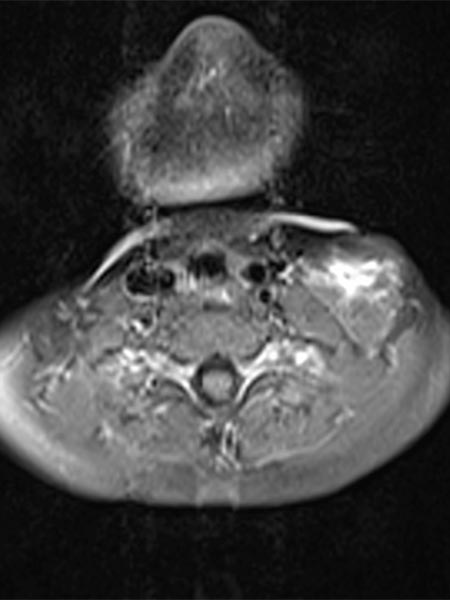

Axial MRI (T2-weighted) also shows the dorsal location of the larger hypointense thrombus within the severely hyperintense venous malformation. In addition, a classic fluid-fluid level within the venous malformation is depicted. The heavier corpuscular components with somewhat lower signal intensity settle dorsally with gravity (dorsal position), the liquid blood serum with somewhat higher signal intensity "floats" up (ventral position), and a fluid-fluid level forms in between.

Axial MRI (T1-weighted) at the same level after contrast administration shows central enhancement within the venous malformation. However, this enhancement is relatively slow (“pooling”) and detectable only minutes after contrast injection and is still incomplete at the time of imaging.